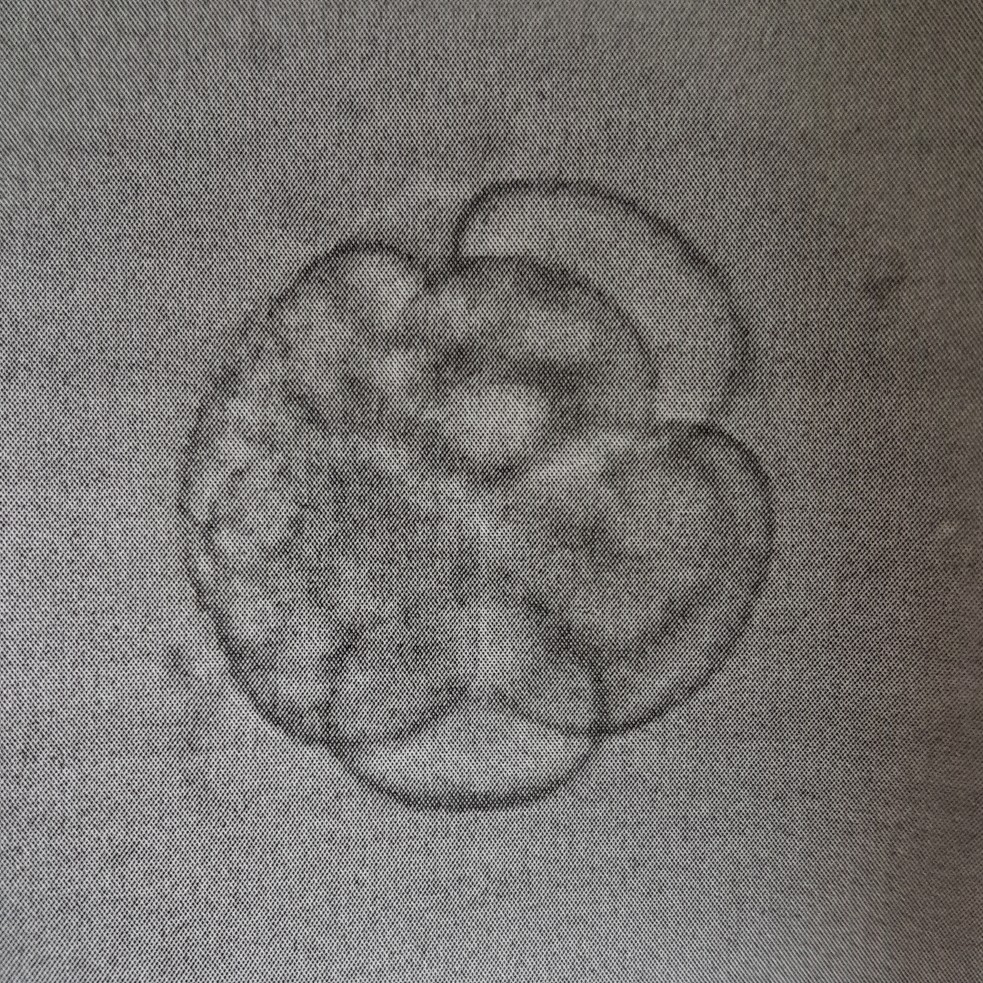

können Sie mir etwas zur Qualität unseres Embryos sagen, Transfer war an PU+2. Das Labor machte uns keine große Hoffnung aufgrund des Grades an Fragmentierung.